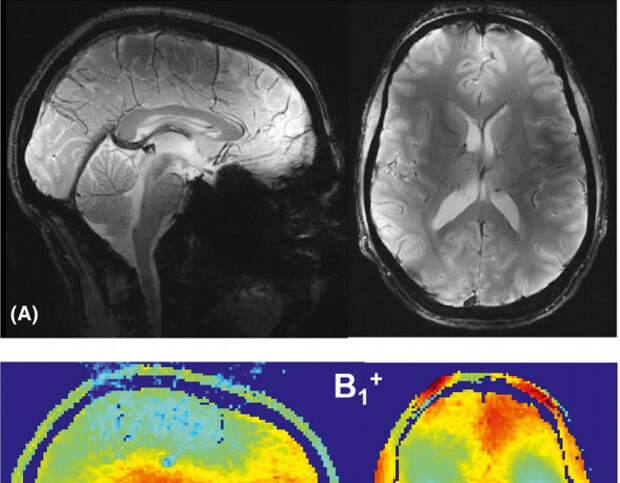

Ученые из ИТМО изменили геометрию диполей, расположив пассивные перпендикулярно по отношению к активным. Также для обеспечения сильной электрической связи между диполями физики переместили пассивный элемент в конец решетки. Прежде чем приступить к созданию новой антенной решетки, исследователи выполнили моделирование, которое позволило оптимизировать структуру. Ее эффективность была протестирована математически и с помощью компьютерной симуляции. Кроме того, физики провели эксперимент, сделав МРТ головного мозга взрослого мужчины. Проверка показала, что подобное расположение диполей решает проблему, связанную с однородностью поля, и связи между активными диполями не появляется.